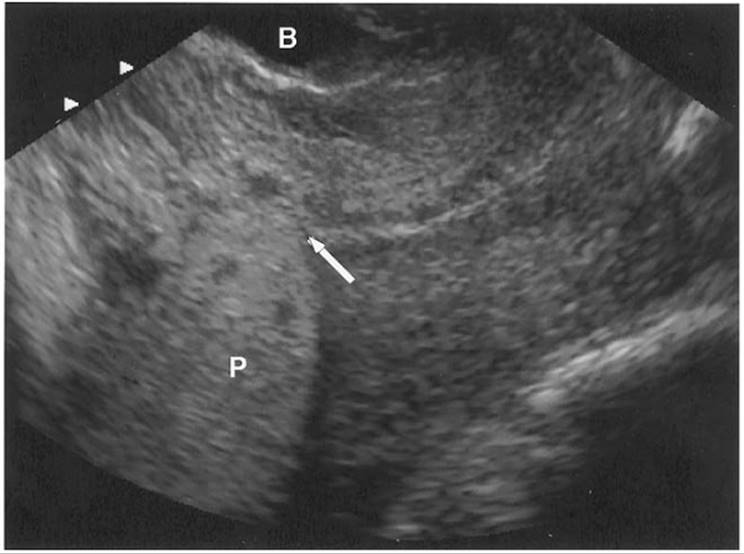

Ultrasound diagnosis is usually performed transabdominally but may be supplemented with transvaginal scanning if the bleeding placental edge is low (Fig. 20.7). Careful examination of the retroplacental area is required. False-positive identification of the normal retroplacental complex, the normal vascular complex of uterine vessels, decidua and myometrium, as an abruption has been reported. This complex appears hypoechoic on ultrasound. Acute bleeding may take on a variety of appearances from hypoechoic to isoechoic to hyperechoic and diagnosis of an abruption may be confused by this complex. The hyperechoic retroplacental complex, which is usually no more than 2 cm in thickness, demonstrates very high amounts of blood flow by color Doppler imaging that excludes its likelihood of being a clot that should demonstrate no active flow. Other hypoechoic areas such as a myoma or a uterine contraction can be mistaken for an abruption but again color Doppler can assist in the distinction because contractions demonstrate a large amount of blood flow within them and myomas demonstrate blood flow around most of their periphery and less within them. A repeat scan of a fresh bleed is often helpful since the ultrasound appearance of a clot will change with time, becoming more echogenic at 48 hours and then hypoechogenic within 1 to 2 weeks. Aside from this retroplacental complex, an abruption is also difficult to distinguish from the placenta itself. Acute hemorrhage tends to be difficult to distinguish from the placenta but with time, the clot becomes hypoechoic compared to the placenta.

FIG. 20.7. Transvaginal ultrasound image of a retroplacental abruption. The markers indicate the size of the clot, 3.5 × 1.0 cm.